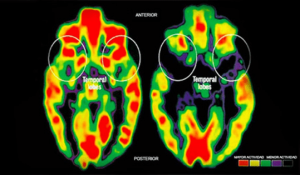

Estudios científicos demuestran que puede generar daños cognitivos tan graves como los que genera la desnutrición. (Reducción del tamaño del hipotálamo, retrasos cognitivos, comprensión del lenguaje, desarrollo psicomotor y motricidad).